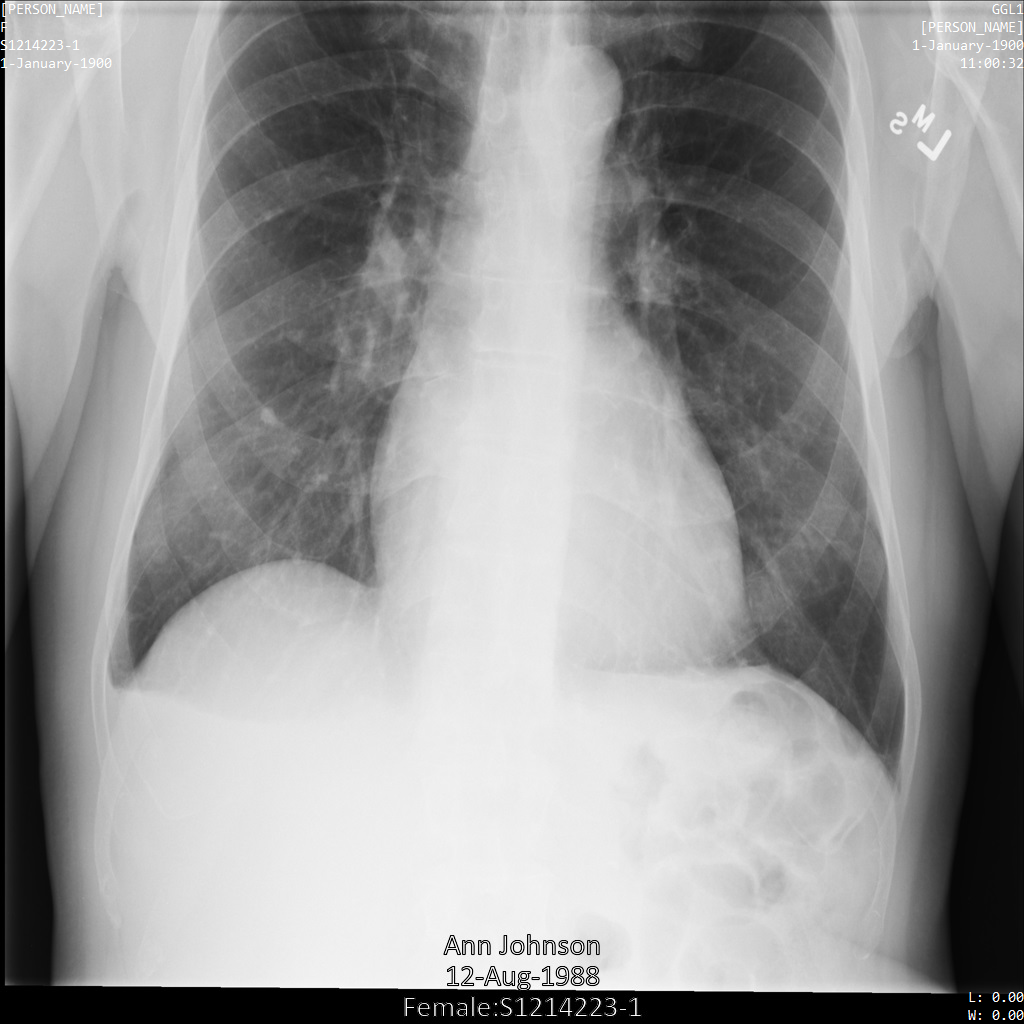

以下各部分提供的示例展示了如何使用各种方法对 DICOM 数据进行去标识化。每个示例都会提供去标识化后的图片输出。每个示例都使用以下原始图片作为其输入:

您可以将每个去标识化操作的输出图片与该原始图片进行比较,以查看该操作的效果。

下图显示了未经遮盖的患者 X 光片:

使用 REDACT_SENSITIVE_TEXT 选项将图片提交到 Cloud Healthcare API 后,图片显示如下:

您可以看到以下情况:

- 图片左下方的

PERSON_NAME已被遮盖 - 图片左下方的

DATE已被遮盖

根据默认 DICOM infoType,该患者的性别不属于敏感文本,因此未遮盖。